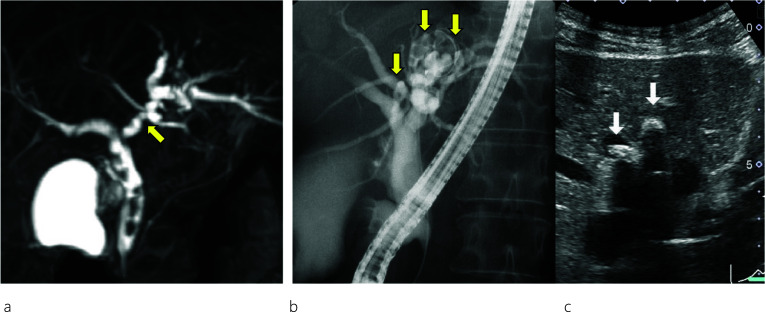

A 45-year-old female patient visited a local hospital with abdominal pain. Blood tests revealed elevated liver enzyme levels, and abdominal computed tomography (CT) revealed dilatation of both the common bile duct (CBD) and intrahepatic bile duct (IHBD). The patient underwent magnetic resonance cholangiopancreatography (MRCP) and endoscopic retrograde cholangiopancreatography (ERCP). MRCP showed CBD stones and stenosis at the confluence of B2 and B3 (Fig. 1a), while ERCP revealed IHBD stones in B2 and B4 (Fig. 1b), which were also observed on abdominal ultrasound (US) (Fig. 1c). Brushing cytology and biopsy at the site of the IHBD stenosis were negative for malignancy. Although the CBD stones were removed, the IHBD stones could not be; therefore, she was referred to our hospital for surgical treatment. Further examination could not be performed around the site of the IHBD stenosis because of impacted stones. Therefore, laparoscopic left hepatectomy was scheduled for suspected intrahepatic cholangiocarcinoma resulting from the impacted stones. However, to properly delineate the anatomy of the liver, enhanced CT was performed, which revealed a dilated IHBD in the left lobe and communication between the right PV and the umbilical portion (Fig. 2a, b). Based on the enhanced CT data, three-dimensional (3D) CT images were reconstructed, which revealed that instead of being located in the left Glisson’s sheath, both the left hepatic artery and bile duct were separated from the left PV (LPV) (Fig. 3a). They also revealed an LPV running through the ventral side of the middle hepatic vein (MHV) (Fig. 3b). Based on these findings, the patient was diagnosed with APB and scheduled to undergo laparoscopic left hepatectomy.